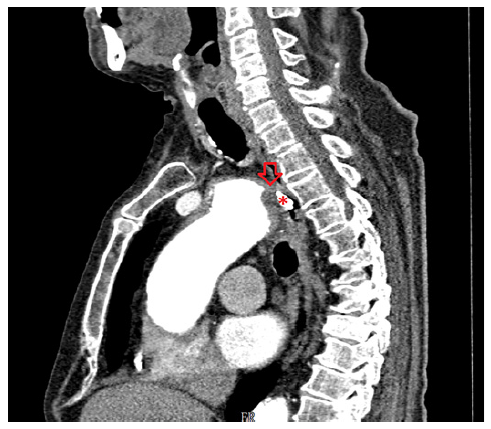

On the eighth day of hospitalization, the patient was readmitted to the intensive care unit in hemorrhagic shock due to new-onset hematemesis. He was intubated and treated with aggressive resuscitation and transfusion of red blood cells. EGD revealed an esophageal 10-mm non-ulcerated mucosal depression with a visible vessel at 20 cm from the incisors (shown in Fig. 1), closed with 3 hemoclips. Thoracic CT angiography showed a brachiocephalic trunk aneurysm with aortoesophageal fistulization (shown in Fig. 2). The vascular surgery department at our hospital and the cardiothoracic surgery department at a tertiary center were consulted, but the patient was deemed unsuitable for endovascular or surgical treatment given the anatomical characteristics of the fistula and his general condition. He subsequently recovered and was able to be discharged home. About 2 months later, the patient was admitted to the emergency room in cardiorespiratory arrest following an episode of hematemesis at home.

CTA is recommended as a first-line noninvasive examination in the suspicion of AEF and is diagnostic in most cases [4, 6]. In our case, the findings on EGD associated to intermittent bleeding raised the hypothesis of Dieulafoy lesion, which was not confirmed by CTA. In fact, the CTA was essential to establish the definitive diagnosis of AEF, as the clinical history and endoscopy findings were not suggestive. We emphasize the significance of performing a thoracoabdominal CTA when investigating the etiology of upper digestive bleeding. This is highlighted by the fact that the initial CTA was abdominal and unremarkable, while the subsequent thoracic CTA revealed the final diagnosis.